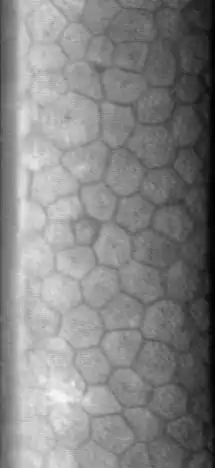

The normal corneal endothelium is a single layer of uniformly sized cells with a predominantly hexagonal shape. This honeycomb tiling scheme yields the greatest efficiency, in terms of total perimeter, of packing the posterior corneal surface with cells of a given area. The corneal endothelium is attached to the rest of the cornea through Descemet's membrane, which is an acellular layer composed mostly of collagen IV.